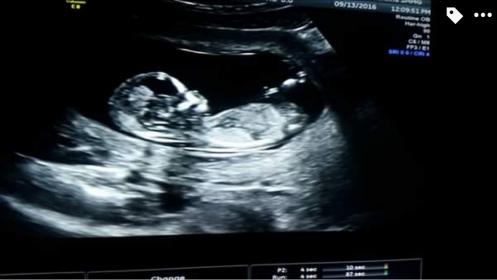

14-15 weeks for a friend

I haven't been on this site for YEARS but you ladies sure helped me out when I was told I was having a boy when in fact I was having a girl!!! yay!!! My princess is now 3 years old!!! Anyhow I have a friend who was told she is Having a certain gender (I won't say which because I don't want to sway you) but I thought I'd run it by some of you self taught nub experts!! Attachment 33163

Girl guess :) unless we were given a picture hiding his junk lol.. I swear I see where the nub has pretty much disappeared into a clitoris

Not the entire nub is shown, more pics?

I thought girl too, but her dr or tech said they think boy, I'm worried she will get her hopes up! She has 4 girls already and is hoping for a boy!!!

Does she plan to find out soon? At 15 weeks I feel the gender should have been obvious to an experienced tech so if they said boy I would lean they are right